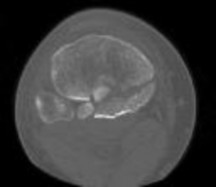

**CLINICAL SITUATION**

Figures 1 and 2 are the radiographs of a 35-year-old man who is brought into the emergency department after a motor vehicle collision. He is complaining of isolated knee pain. Examination reveals swelling, blood filled blisters, popliteal ecchymosis, joint line pain, and limited knee joint motion. His pulses and sensation are normal.

Figures 3 through 8 are the axial and sagittal CT scan sections of the injury. Intra-operative patient positioning for definitive fixation should be